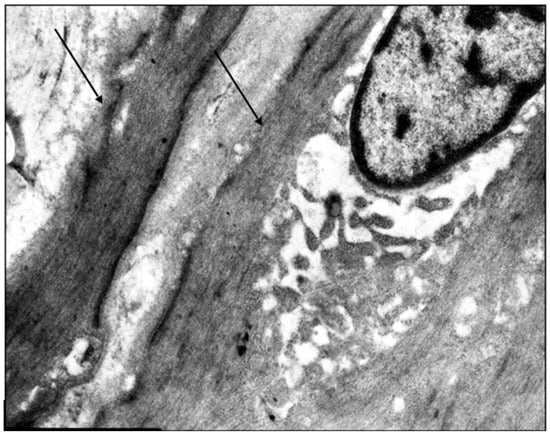

Middle-aged patients with VD demonstrate myoelastofibrosis and diffuse sclerosis within the venous wall, marked by expanded connective tissue layers between muscle bundles. Ultrastructural analysis reveals disorganized collagen fibrils and elastic fibers interspersed among phenotypically heterogeneous smooth muscle cells. In patients with decade-long varicose disease, electron microscopy identifies distinct “light” and “dark” myocytes (Figure 4). The “light” variants show reduced contractility due to organelle disarray and myolamellar breakdown, while “dark” cells display compressed, electron-dense cytoplasm with deformed myofilaments, reflecting cellular dysfunction and impaired intercellular communication.

Figure 4. Fragment of the great saphenous vein in the second age group with a disease duration of more than 10 years. Transmission electron microscopy. (a)—collagen fibrils (black arrow) between “dark” smooth muscle cells (white arrow) and unchanged smooth muscle cells (asterisk) magnification × 12,000; (b)—“light” smooth muscle cells. Magnification × 14,000.